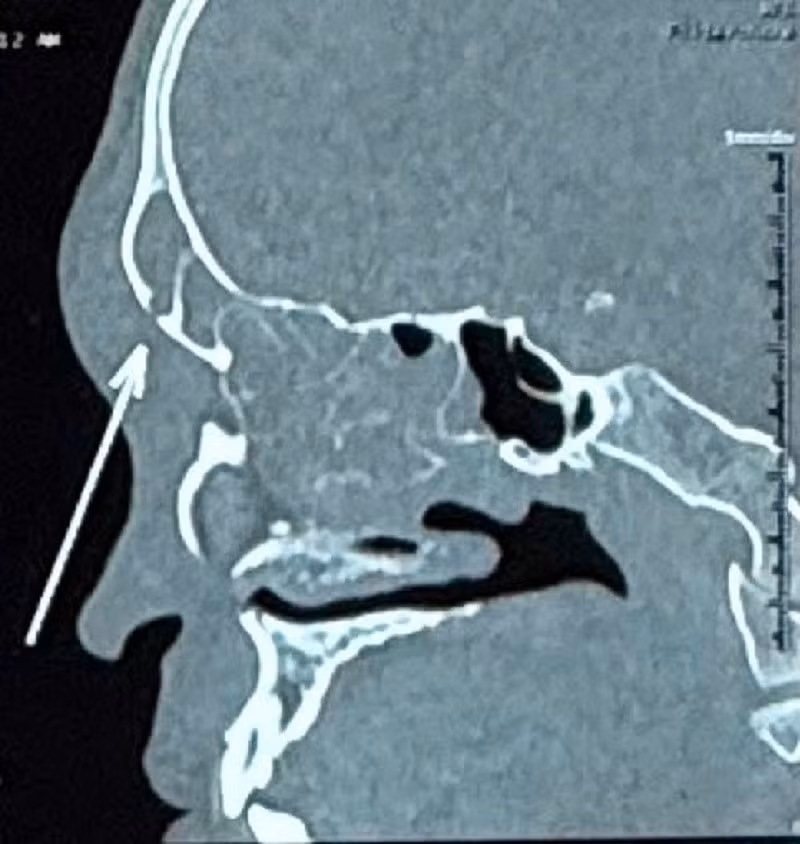

Vị trí xương vùng trán của người bệnh bị khuẩn tụ cầu phá hủy

Qua thăm khám bác sĩ ghi nhận vùng trán bên phải của người bệnh sưng lớn, đau. Kết quả nội soi mũi cho thấy có nhiều dịch mủ đục. Kết quả chụp CT phát hiện, người bệnh bị viêm đa xoang hai bên. Đặc biệt có dấu hiệu viêm lan ra phần mềm vùng trán và hình ảnh khuyết xương thành trước xoang trán (biến chứng Pott's Puffy Tumor).